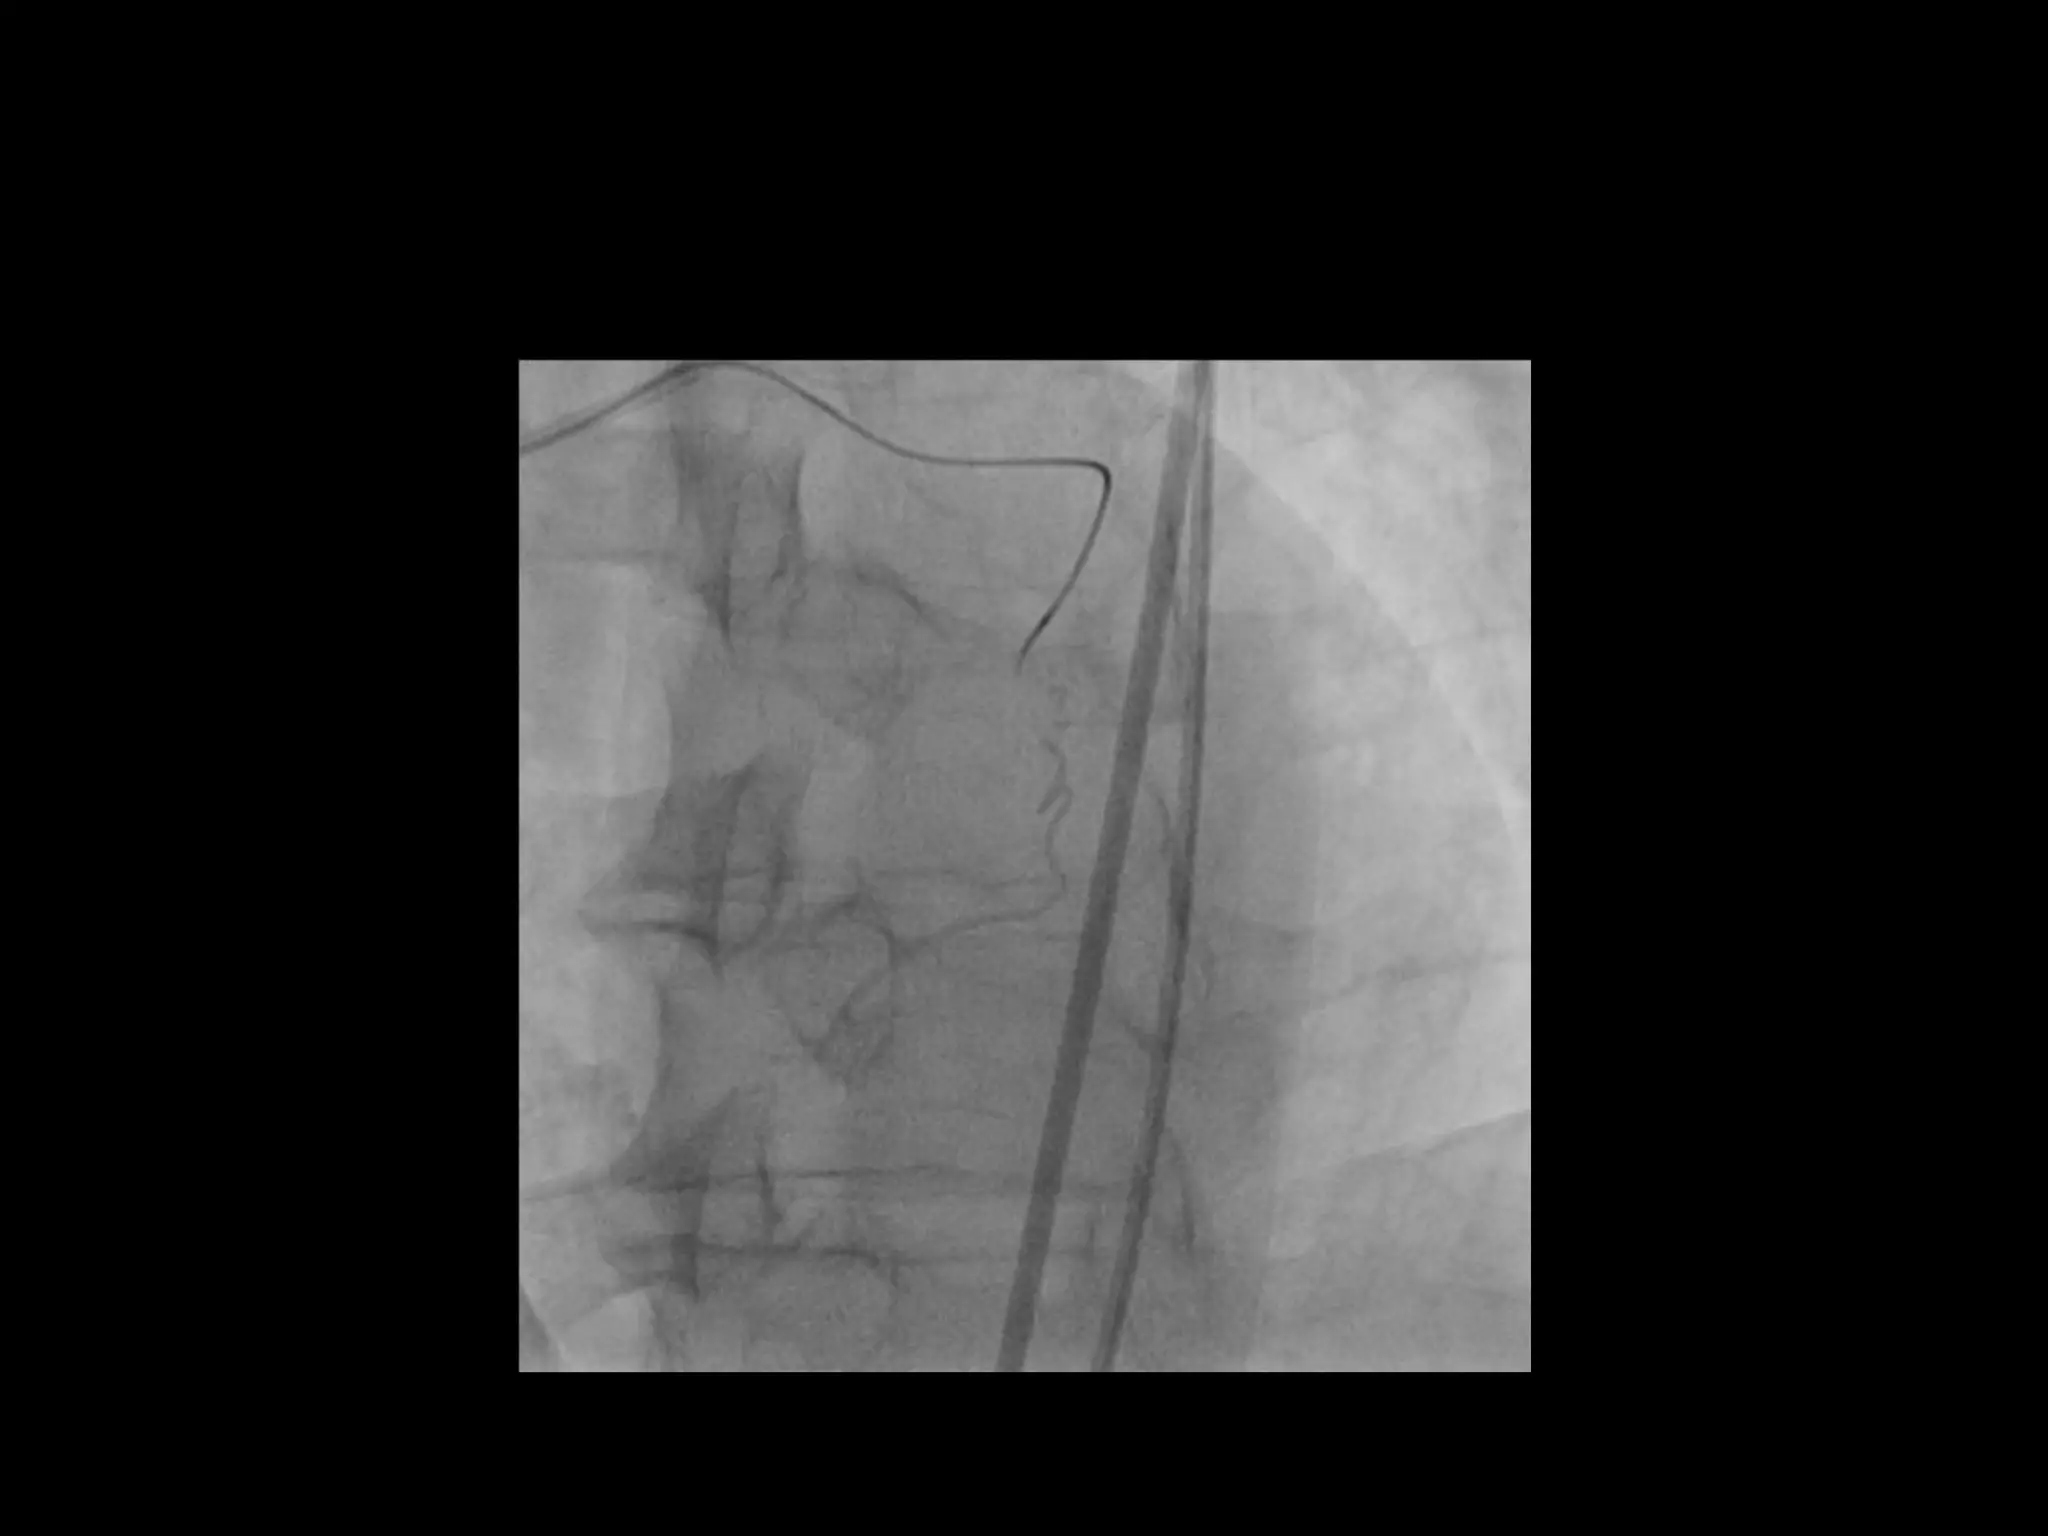

This document provides guidance on evaluating the feasibility of percutaneous coronary intervention (PCI) for a chronic total occlusion (CTO). Key factors to consider include: the patient's tolerance for a long procedure, contrast load, and radiation exposure; the CTO's proximal cap ambiguity, length, distal landing zone, and presence of interventional collaterals; and ensuring good quality angiography. With adequate planning and use of appropriate CTO techniques, feasibility is nearly always present for symptomatic patients. Success rates of CTO-PCI are reported to be 94% when using a planned approach.